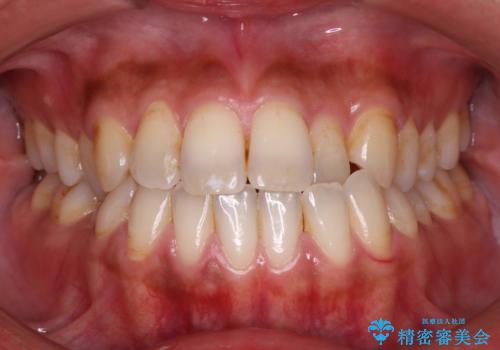

Invisalign インビザライン によるガタつき、受け口傾向の改善

奥歯の位置関係の修正は難儀することが多いマウスピース矯正ですが、割とスムーズに奥歯の位置関係の修正をすることができました。

クロスバイトもきれいになり、きれいな歯並びとなりました。